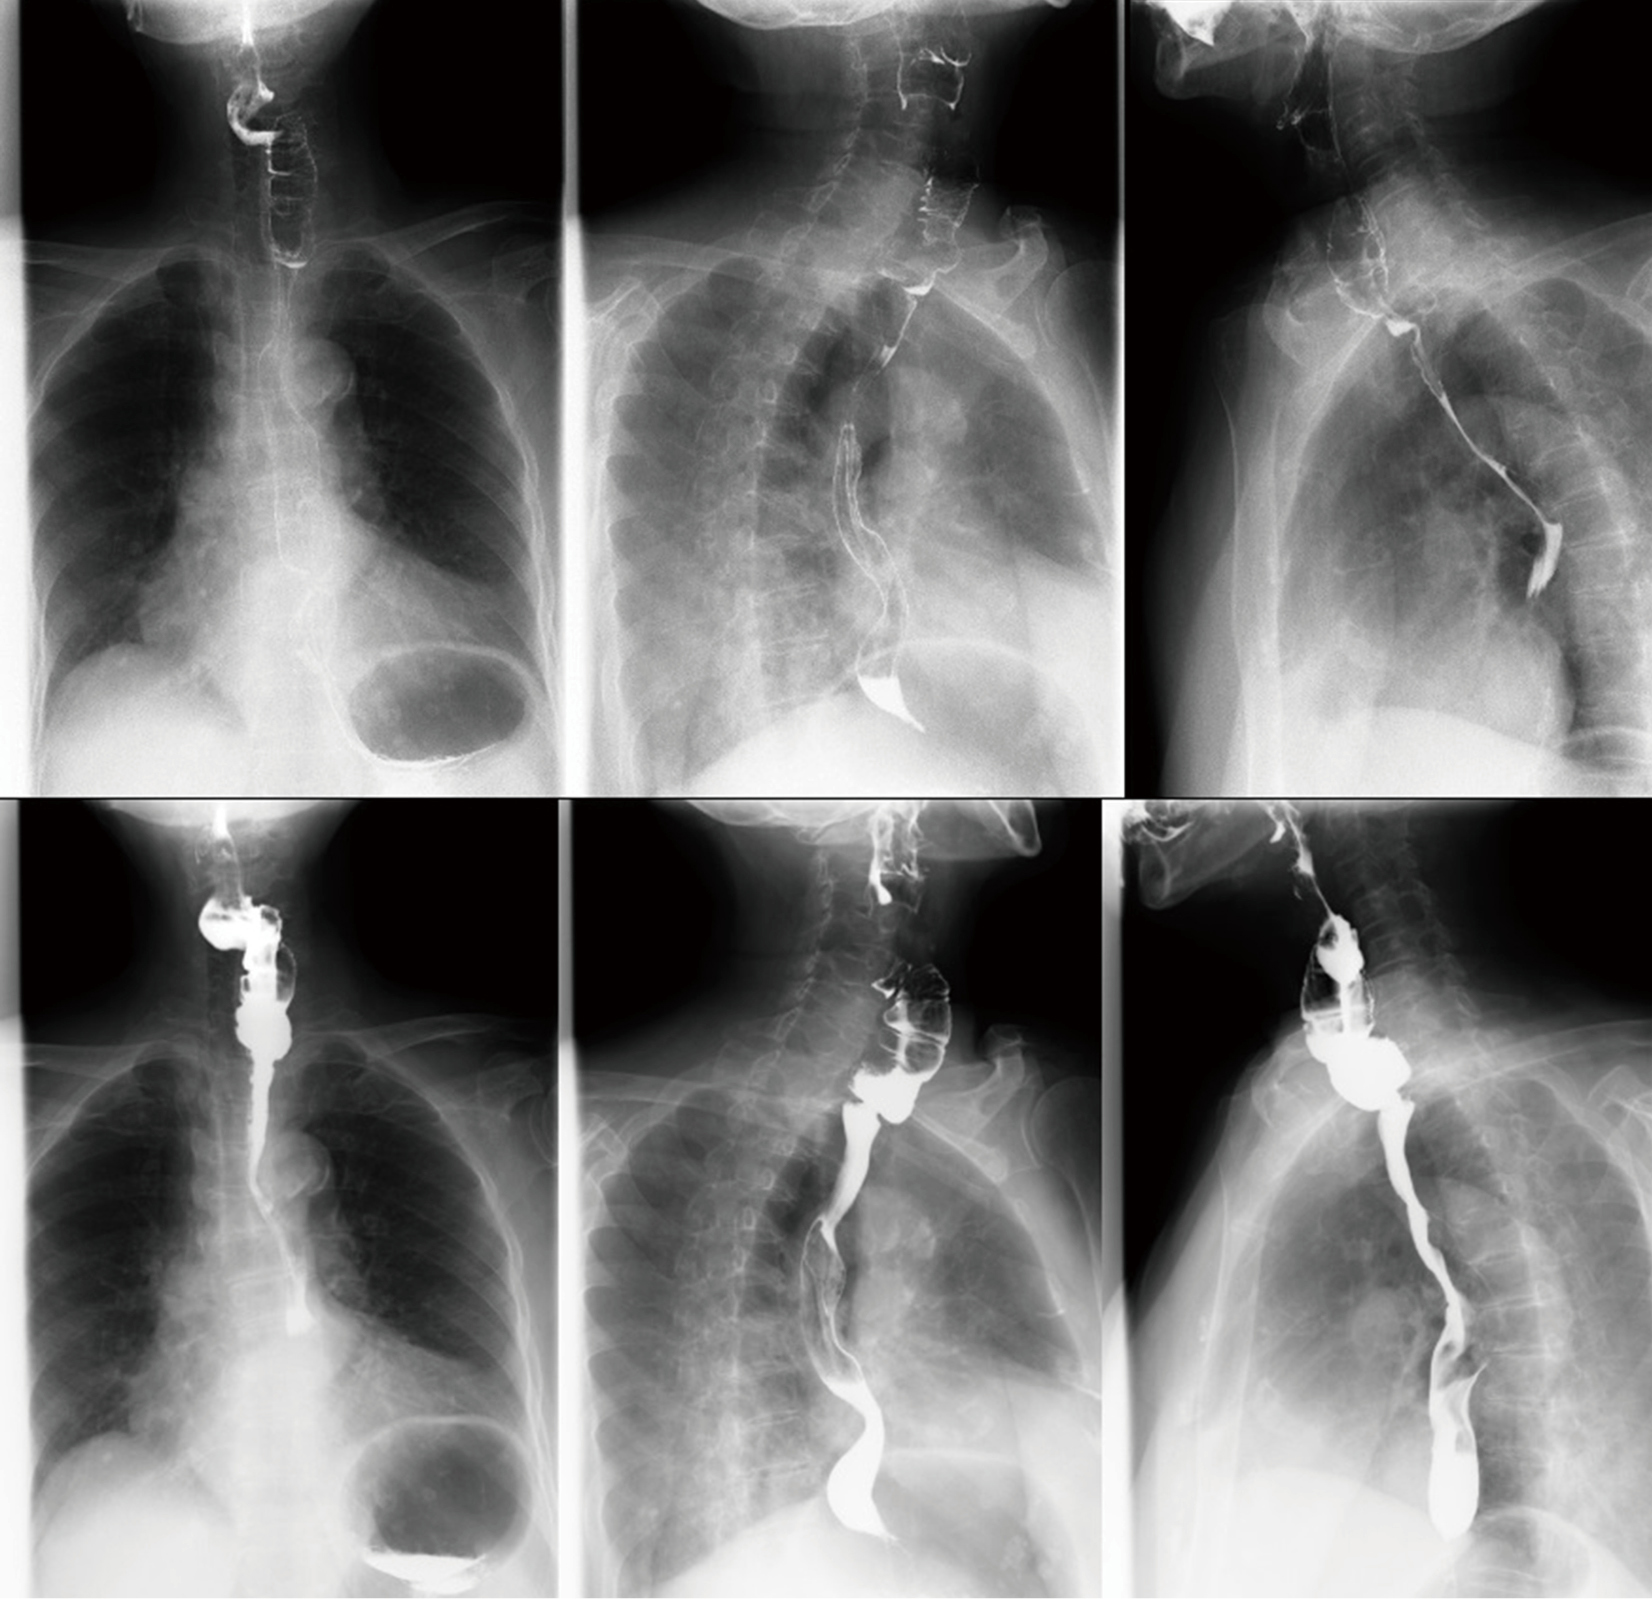

Reconstruction with free jejunal interposition. A) Gastroscopy and

Reconstruction with free jejunal interposition. A) Gastroscopy and Jejunal Interposition Esophagectomy Free jejunal transfer may be used as a conduit in cervical. Colon interposition and free jejunal flap for esophageal reconstruction are the alternative choices when the gastric tube is not. The supercharged pedicled jejunal interposition is another acceptable conduit alternative to the stomach. Esophageal continuity after esophagectomy can be. Jejunal interposition is a valuable replacement conduit for the lower esophagus.. Jejunal Interposition Esophagectomy.

Reconstruction with free jejunal interposition. A) Gastroscopy and Jejunal Interposition Esophagectomy Colon interposition and free jejunal flap for esophageal reconstruction are the alternative choices when the gastric tube is not. This is because preparing a. Jejunal interposition is the third most commonly used method for esophageal reconstruction. The supercharged pedicled jejunal interposition is another acceptable conduit alternative to the stomach. Esophageal continuity after esophagectomy can be. Pedicled jejunum has been used. Jejunal Interposition Esophagectomy.